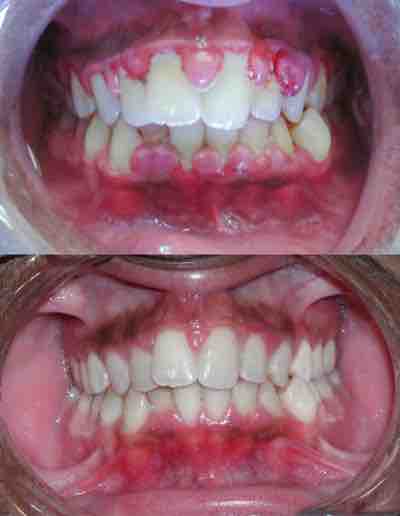

Gingivitis

Severe gingivitis before (top) and after (bottom) treatment.

In some people, gingivitis progresses to periodontitis –- with the destruction of the gingival fibers, the gum tissues separate from the tooth, forming pockets between the tooth and gum. Subgingival microorganism (those that exist under the gum line) colonize the periodontal pockets and cause further inflammation in the gum tissues and progressive bone loss.